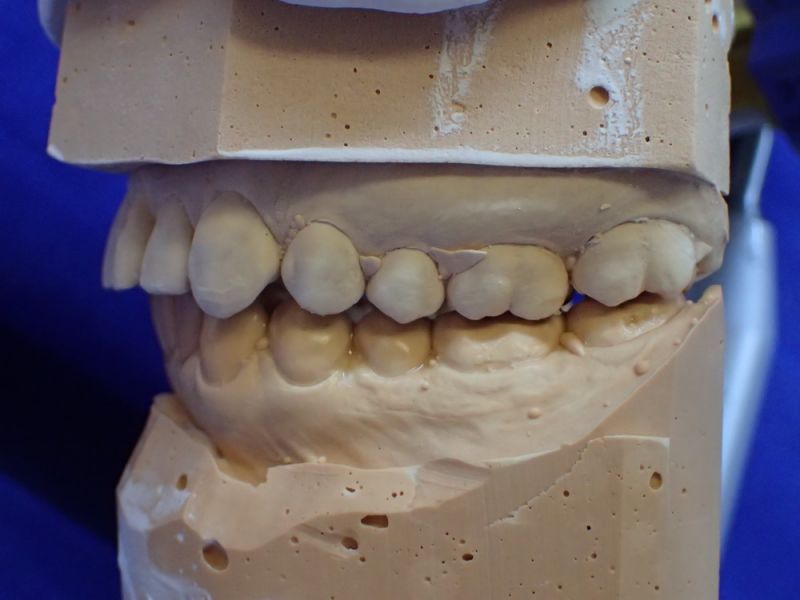

Mann kann hier sehr gut an den beiden Punkten der distalen Dreipunktabstützung erkennen, mit welch hoher Passgenauigkeit die Zentrikplatten auf die Gipszähne der Meistermodelle aufgebacht werden können und müssen.

Es ist einer dieser Detailpunkte, der darüber entscheidet, mit welcher Anfangspassgenauigkeit ein 'A'ufbissbehelf am Ende eines langwierigen Arbeitsprozesses in der Mundhöhle des Patienten eingeglidert werden kann.